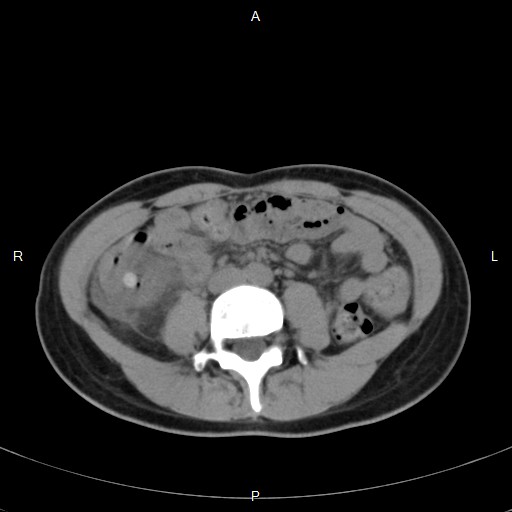

在沒有注射顯影劑的升結腸可見一高亮度的糞石和週邊的發炎變化,

在注射顯影劑的CT下,可以看到卡在憩室的糞石週邊有一些液體和氣體存在。